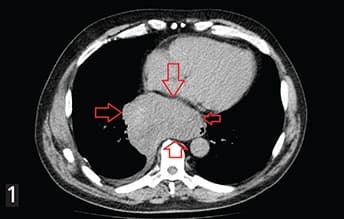

Рисунок 1. ГИСО нижней трети пищевода.ГИСО возникают в любом месте ЖКТ. Общие первичные очаги включают: